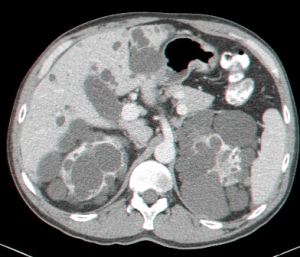

בטומוגרפיה ממוחשבת ניתן לראות מילוי של חומר ניגוד בהמנגיומה (תצלומים 15.10-17.10).

בבדיקות מעבדה: תפקודי הכבד לרוב תקינים, אך תיתכן עליה קלה ברמת האנזימים. האבחנה מתבצעת על ידי טומוגרפיה ממוחשבת (תמונה 26.10 ) או תהודה מגנטית (תמונה 27.10) כך שבדרך כלל אין צורך לקחת ביופסיה. באולטרה-סאונד ניתן להדגים גוש בכבד (תמונה 28.10).